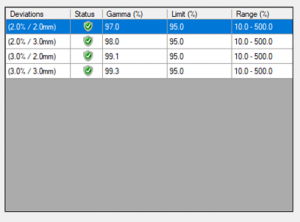

Get your gamma pass rate based on different dose deviation and DTA criterion.

Get your gamma pass rate based on different dose deviation and DTA criterion.